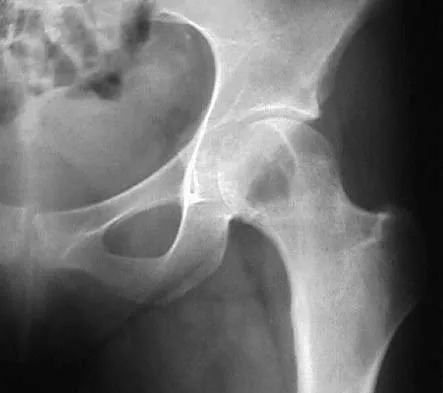

Figure 11 shows the radiograph of a 26-year-old man with type I diabetes mellitus who was struck by a motor vehicle. What is the most common complication associated with this pelvic fracture?

The most common complication following acetabular or pelvic ring injury is deep venous thrombosis (DVT). Without prophylaxis, rates of DVT are as high as 70% to 80%. With prophylaxis, the rates are around 10%. Infection rates in surgical repair of acetabular fractures are relatively low but a history of diabetes mellitus and a significant Morel-Lavalle lesion certainly increase the risk. However, even with these two complicating factors, the rates of infection are still lower than 10%. Sciatic nerve palsy rates from the injury alone approach 20% and iatrogenic injury is usually less than 2%. Degenerative changes to the hip following this injury approach 20% to 25%, even with an anatomic reduction. Geerts WH, Code KI, Jay RM, et al: A prospective study of venous thromboembolism after major trauma. N Engl J Med 1994;331:1601-1606.